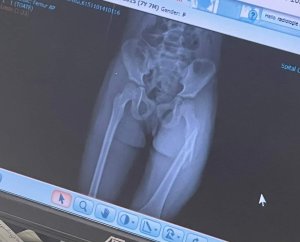

Aceasta este ecografia Amaliei, ruptură de femur, operație de urgentă.